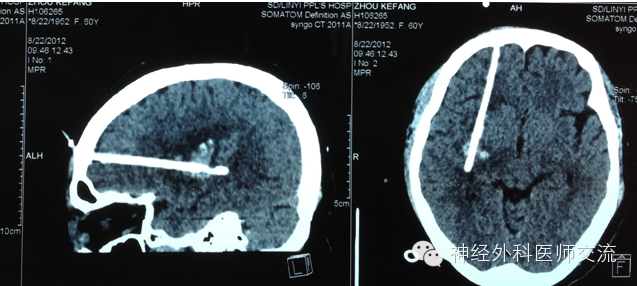

(2)CT图片处理——穿刺点的选择及介入手术入路

① 确定穿刺平面:据CT所显示的血肿,选择血肿最大断层,即为要穿刺的平面,也就是说:操作时要将引流导管沿着这一血肿最大层面进入血肿腔内。确定该层面至颅底层面的距离(即厚度)(X毫米:一般为50~60 mm)。

② 确定穿刺点:在血肿的最大层面上划出血肿的最大长轴线,与前额头皮的交点即为理论穿刺点,测出该点至血肿远端的距离(毫米),该数值减去5mm~10mm即为置管深度,一般为80~120mm。

确定实际穿刺点要做到两个避开:避开额窦、避开上矢状窦!实际穿刺点,一般为正中矢状线旁开15mm~20mm,内眦上方45mm~60mm的前额之交点,多为55mm。

置入引流导管之概要:

1.确定穿刺点,但过一点可做无数条射(直)线;

2.确定穿刺平面,即血肿的最大CT段层面,再将经过穿刺点的射线,局限在穿刺平面内;

3.确定最优路径,在穿刺平面内选择经过穿刺点,且基本为血肿最大长轴线的那条射线。

具体操作时,就是将引流导管经过穿刺点的骨孔,沿着该条假设的射线进入血肿腔的远端。